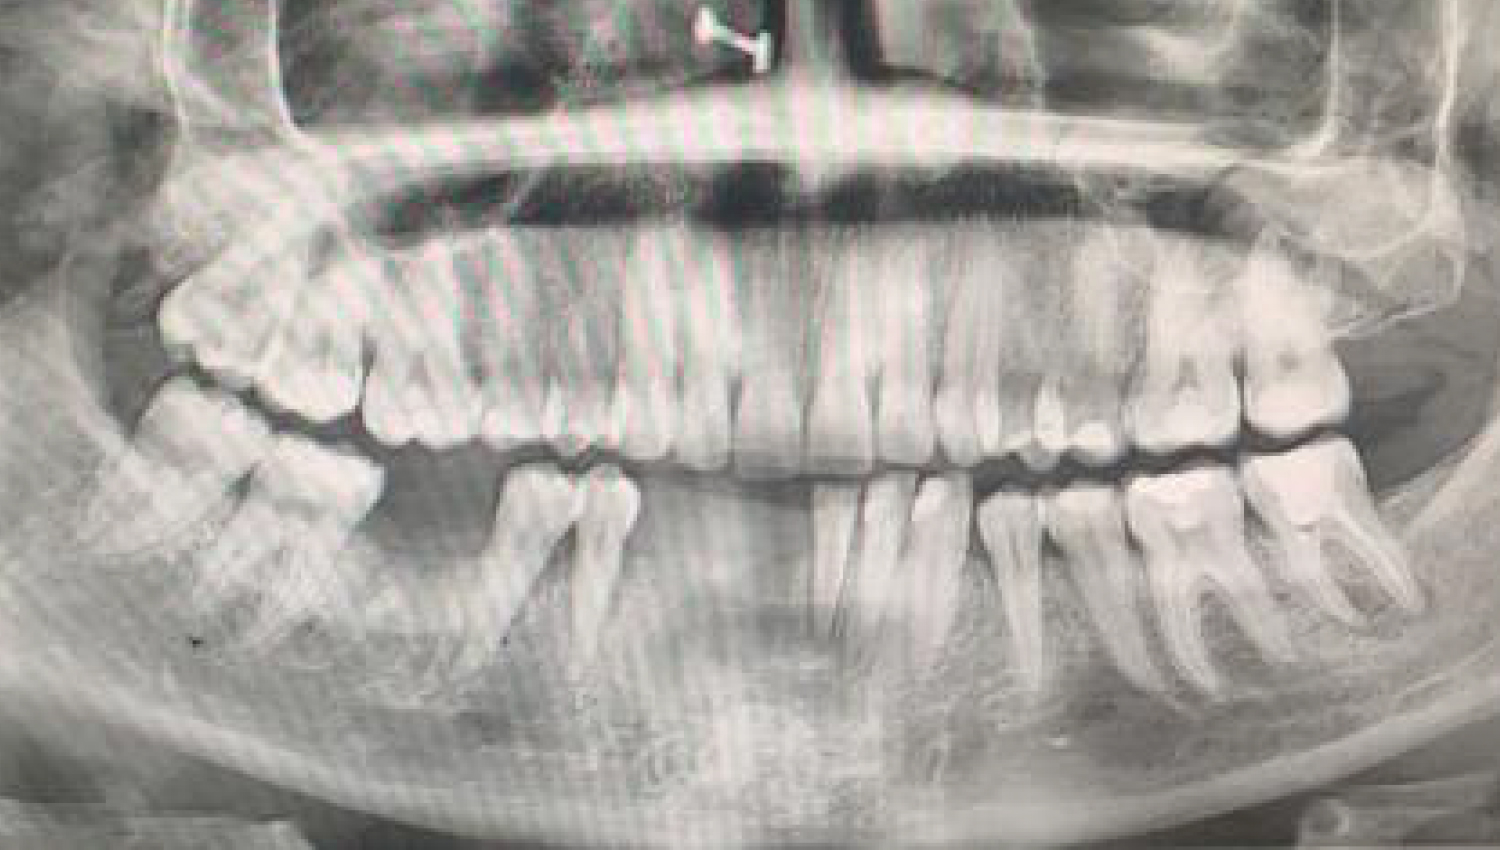

1.Initial radiological view.